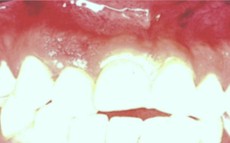

Paciente

femenino que presenta edema e hinchazón en lado derecho de la cara.

Durante el examen clínico se encontró en la pieza #12 movilidad, dolor a la

percusión, dolor a la palpación y profundidad al sondeo por vestibular,

por donde estaba produciéndose el drenaje (fístula periodontal), los

mismos síntomas y signos clínicos, excepto la profundidad al sondeo, presentaba

la pieza #11, además de presentar deficientes restauraciones de resina por

palatino. Radiográficamente se observó tratamientos de conductos con

obturaciones deficientes (sobreobturación de un cono en pieza #11) y la

existencia de una sombra radiolúcida a nivel periapical de la pieza #12.

(Figs.: 1, 2, 3).